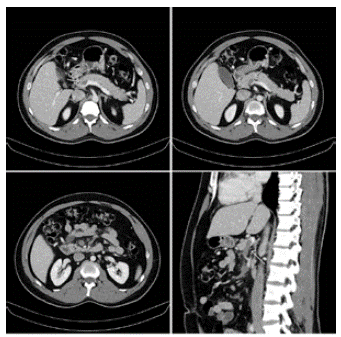

El paciente ingresa por segunda vez al servicio de urgencias diez días después del accidente, refiriendo cuatro días de náuseas constantes, distensión abdominal, dolor tipo cólico en epigastrio e hipocondrio derecho, de predominio postprandial, gravativo y que empeora con los cambios de posición en el decúbito. Al examen físico sus signos vitales eran normales, no se evidenciaban estigmas de trauma toracoabdominal pero la palpación del abdomen superior era notablemente dolorosa, por lo que se decidió realizar una tomografía computarizada (TC) de abdomen total con contraste endovenoso. En la misma se documenta trombosis de la vena mesentérica superior y de la rama distal de la porta derecha, sin evidencia de lesiones traumáticas en órganos sólidos ni vísceras huecas (figura 1).

Figura 1 Estriación de la grasa mesentérica rodeando vasos mesentéricos superiores, con trombosis de la vena mesentérica superior y trombosis de la rama distal de la porta derecha en su rama anterosuperior.

Actualmente se considera la TC con contraste venoso como el método diagnóstico de elección, debido a sus costos más bajos en comparación con la resonancia magnética, su amplia disponibilidad y su excelente sensibilidad3-5,13. Los hallazgos tomográficos incluyen asas intestinales dilatadas y engrosadas, estriación de la grasa mesentérica, ascitis, un halo o aspecto blanco del intestino, defectos de llenado de los vasos y neumatosis intestinal3,5,15. La TC presenta como ventajas el no ser operador dependiente, la posibilidad de identificar otras lesiones asociadas, así como la extensión exacta de la trombosis, y detectar signos de isquemia intestinal 8,18.